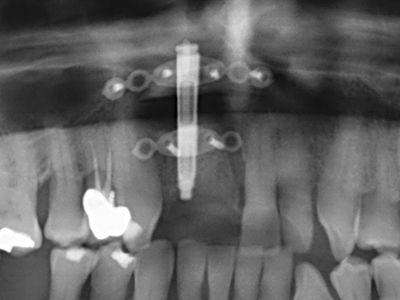

Fig. 11: The postoperative panoramic image shows the vertical augmentation and sinus floor elevation.

Fig. 15: The one-year follow-up x-ray examination shows stable conditions at the bone level.